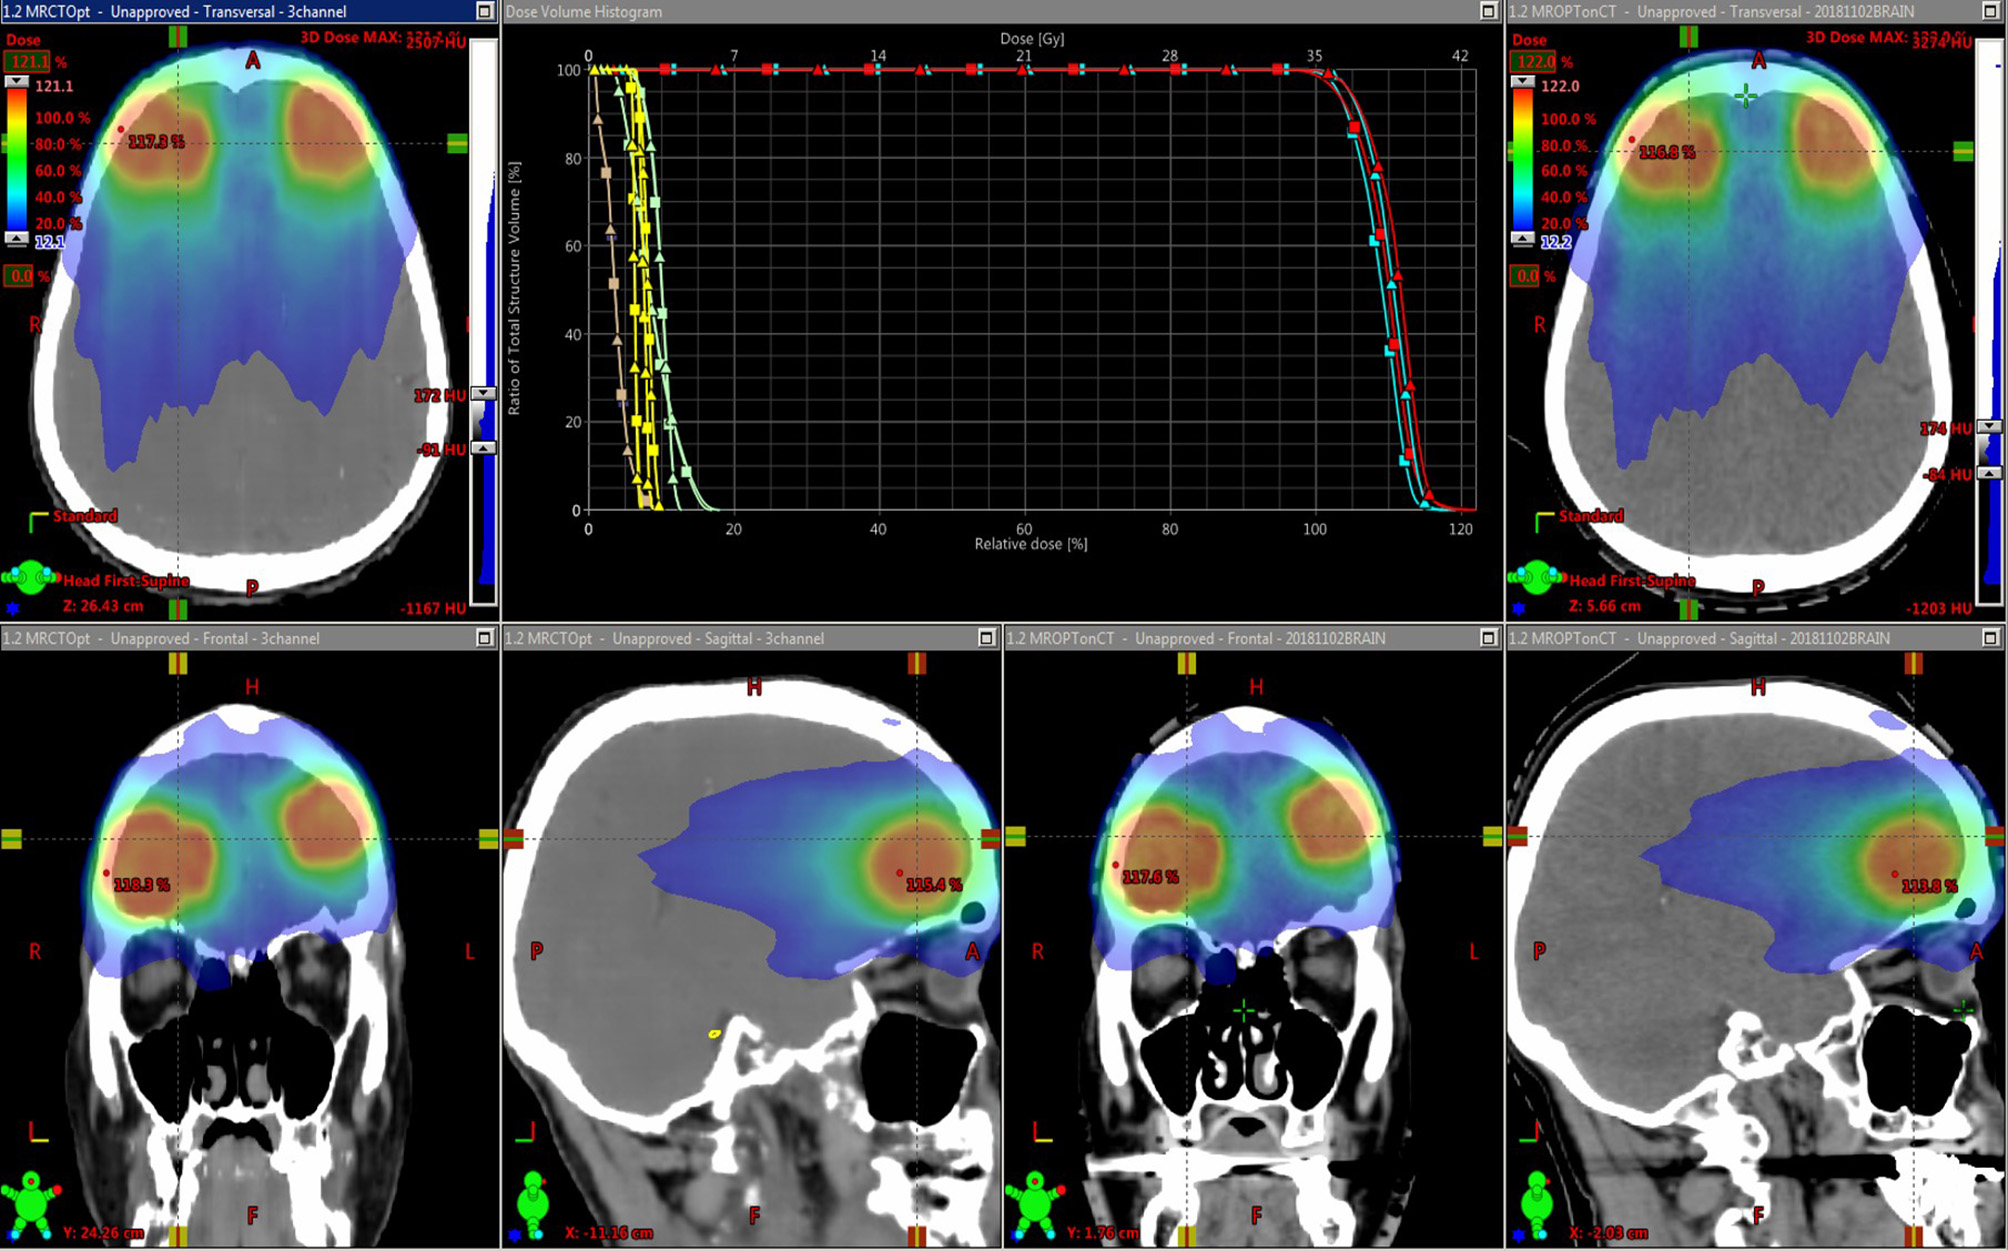

Figure 5 shows an example treatment plan comparison. The PTV mean dose values had a systematic difference of 2.3% (σ 0.1%) between the plans generated using the MRCT-defined density grids and recalculated using the CT-defined grids. As can be seen on the images, the MRCT was not trained to reproduce the immobilization device present on the CT, and thus these differences are expected due to the added attenuation of the mask.

FIGURE 5

www.frontiersin.org

Figure 5. Dose distributions for intensity modulated treatment plans for two targets. The original plan was optimized using the MRCT-derived density grid (left), and the resulting beam fluences were used to recalculate doses on the CT-derived density grid (right). Dose volume histograms (DVHs) for the Brainstem (yellow), Optic chiasm (brown), eyes (green), and two targets (light and dark blue) are shown. Squares represent MRCT plan DVH curves, and triangles come from recalculated plans using CT.